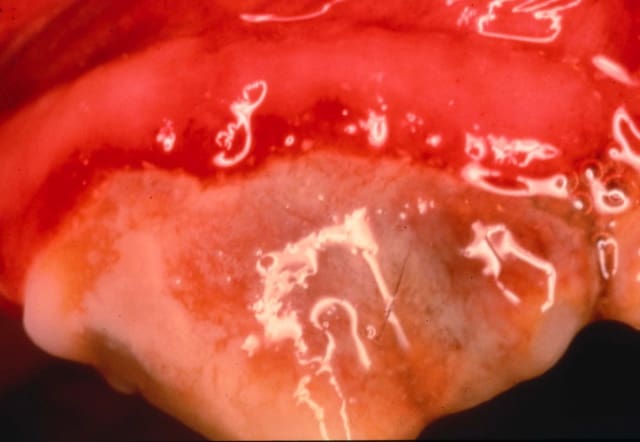

Periodontitis is inflammation of the periodontal tissues below the gum. It is characterized by loss of the gingival attachment and bone surrounding the tooth. With periodontitis and attachment loss, pockets around the teeth form. The pockets that form below the gumline provide a place for more bacteria to live. Inflammation in response to bacteria sitting within the pockets below the gumline further contributes to bone and tissue loss. Eventually, periodontitis will become irreversible. Pain, infection, abscesses, tooth loss, and in severe cases, jaw fracture may occur.

Significant gingivitis and bone involvement is present. Teeth are becoming mobile as moderate calculus, gum recession, and gingival pockets  are also noted. Irreversible tooth damage may be present and these patients often require advanced periodontal therapy or oral surgery.